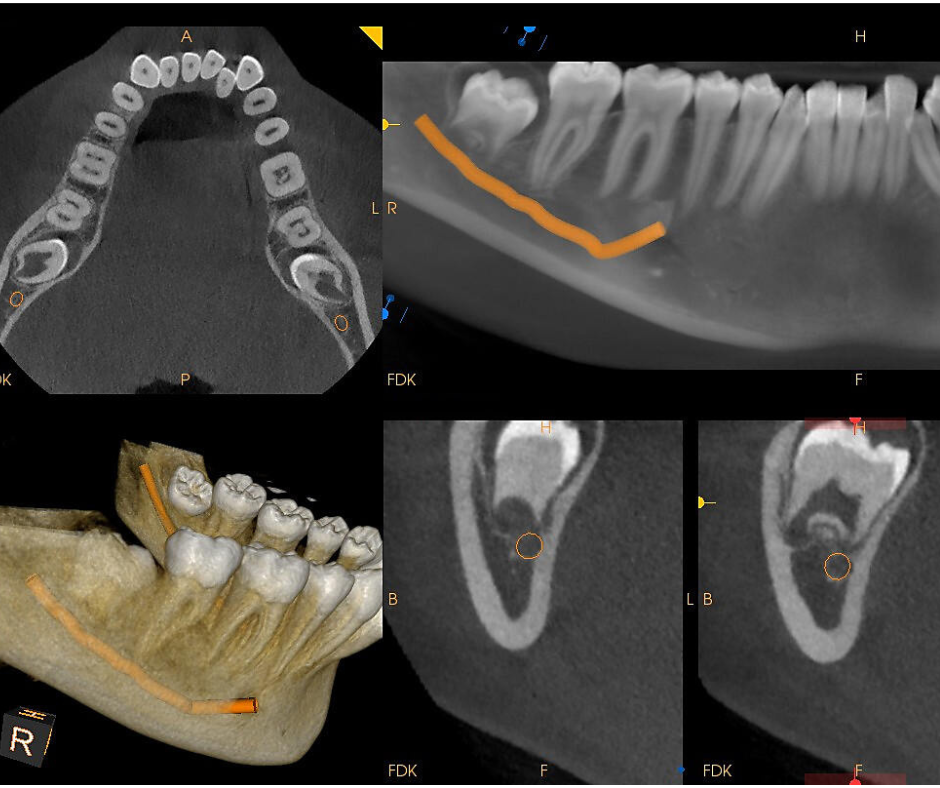

A full-arch dental implant restoration is a life-changing solution for patients who are missing most or all of their teeth, offering a stable, fixed alternative to dentures. Using as few as four to six strategically placed implants, we support an entire upper or lower arch of natural-looking teeth that stay securely in place—no slipping, adhesives, or nightly removal. At National Dental Implant Center of Hauppauge, we use advanced CBCT imaging, digital planning, and guided surgical techniques to ensure each implant is positioned with exceptional accuracy for long-term success. This modern full-arch approach restores full chewing ability, enhances facial support, and delivers a confident, functional smile that looks and feels completely natural.

Beyond aesthetics, full-arch implant restorations are designed to protect long-term oral health and facial structure. When multiple teeth are missing, the jawbone naturally shrinks over time, leading to a sunken appearance and changes in bite alignment. By placing implants that integrate directly with the bone, we restore essential support, stimulate bone retention, and create a strong foundation for a long-lasting smile. At National Dental Implant Center of Hauppauge, our digitally guided workflow ensures every step — from implant placement to final bridge design — is executed with exceptional precision. The result is a durable, functional, and natural-looking full-arch restoration that allows patients to eat, speak, and live with complete confidence.